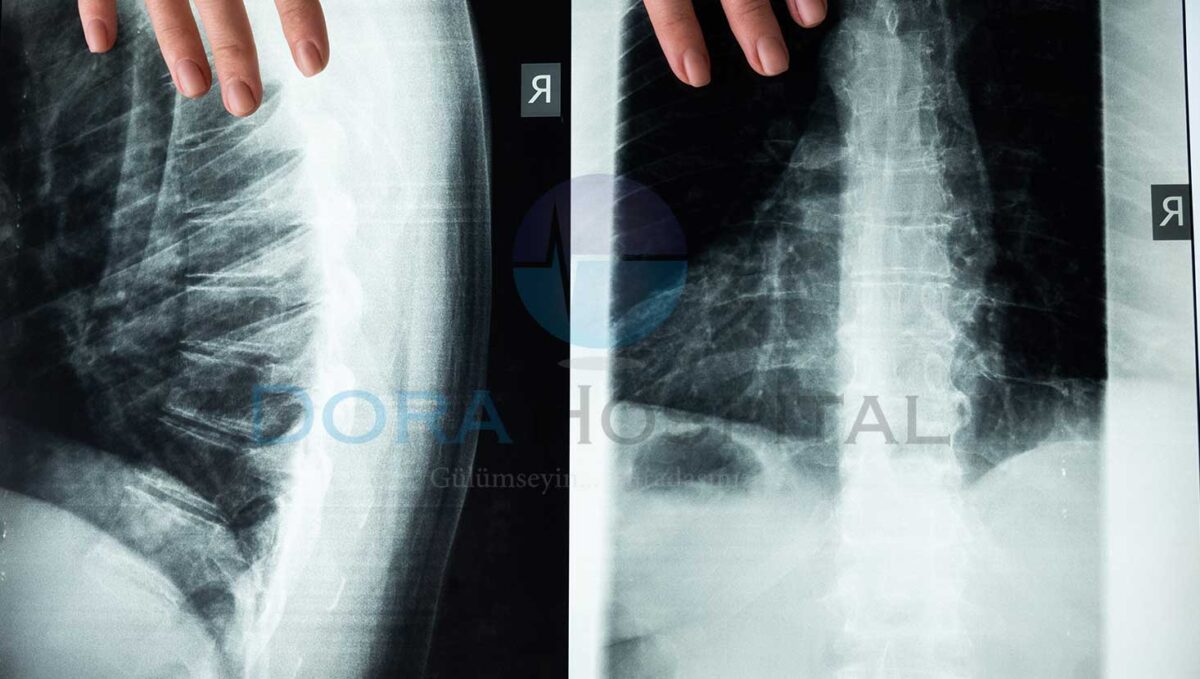

Omurga stres kırığı genellikle başka bir hastalık sonucunda hekimlere başvurularak ortaya çıkmaktadır. Ancak belirti sonucunda başvurulması durumunda hekim ilk olarak hastanın öyküsünü almaktadır. Daha sonrasında ise fiziki muayenelerini gerçekleştirerek tahmini kırığın nerede olduğunu düşünmektedir. Buna bağlı olarak da röntgen veya bilgisayarlı tomografi ile kırığın nerede olduğu ve ne kadar bir alanı etkilediği görüntülenmektedir.

Strest kırığına bağlı olarak bazı kişilerde bel kaymaları da meydana gelmektedir. Bu gibi bir durumdan şüphelenilmesi durumunda ise film istenmektedir. Ancak bu film ile istenilen şekilde görüntüleme sağlanamaması durumunda ise sintigrafi veya BT istemek mümkün olmaktadır. Tanının net bir şekilde koyulduktan sonra tedavi planı için ise MR çektirmek mümkün olmaktadır.

Kişilerde kayma ile birlikte bacak ağrısı veya uyuşma gibi belirtiler bulunması durumunda ise hastalarda omurilik ve sinirlerin durumunun nasıl olduğunu belirlemek için ise MRG yapılması istenebilmektedir. Ancak bu her hastada uygulanacak bir yöntem olmamaktadır. Gerekli olan tetkik ve değerlendirmelerin yapılması sonucunda tanının koyulması ile birlikte tedavi planı gerçekleştirilmektedir.